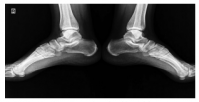

Dose reduction was used in patients with moderate and severe back pain, constituting 37.2% of the patients describing the complaint. The vast majority of these patients responded to dose reduction, while eight (10.2%) patients needed to use non-steroidal anti-inflammatory drugs for pain relief. Sacroiliitis was present in four (4%) patients, including three females and one male. There was no statistically significant difference between the sexes for sacroiliitis development (p=0.25). Bilateral sacroiliitis was detected in one patient (Figure 1). Sacroiliitis regressed 1.5 to 2.5 months after isotretinoin treatment cessation in all patients. The patients diagnosed with sacroiliitis were followed for six months. Three (3%) patients described myalgia, which was of mild severity and did not require additional treatment. Among these patients, two female patients also described low back pain. Creatine kinase (CK) elevation was observed in 18 (18.1%) patients, including 13 males and two females, one to three months after the beginning of treatment (p=0.1). The elevated CK values ranged between 233 and 940 IU and returned to normal levels after dose reduction. One (1%) female patients who was on low-dose isotretinoin treatment (0.5 mg/kg) was diagnosed with enthesitis at three months of treatment (Figure 2).